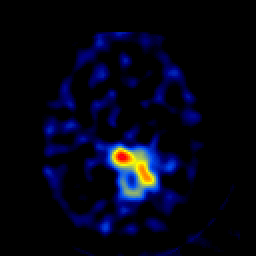

SPECT TL Study #4 -- Slice #38

[Home][Help][Clinical][Tour 1][Tour 2][Tour 3] Slice 38